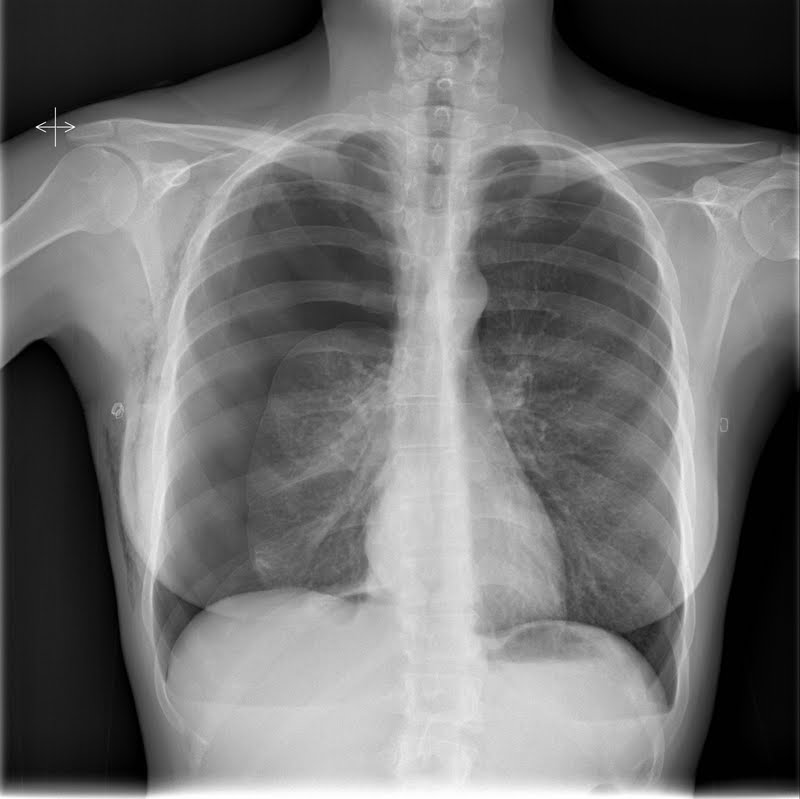

2.- Varón de 21 años, acude al SUH por clínica desde hace 24 horas de dolor abdominal, inicialmente periumbilical, con posterior irradiación hacia FID, acompañado en las últimas horas de fiebre y afectación del estado general.

EF: Tª: 37,8 ºC; abdomen doloroso a la palpación en FID, signos irritativos.

El diagnóstico es lo que parece, pero os dejamos la radiografía simple de abdomen que se le realizó para que nos deis vuestra opinión sobre ella.

ResponderEliminar2)apendicitis aguda.Apendicolito

2) Apendicitis aguda. Fecalito apendicular.

ResponderEliminar2.- Apendicolito en paciente con apendicitis aguda.